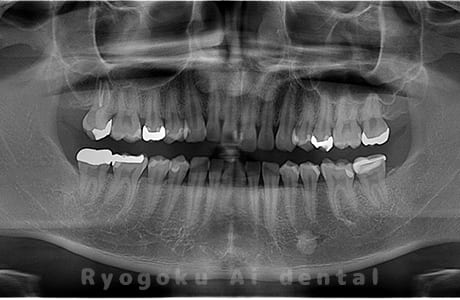

水平埋伏の親知らず

歯茎の中で完全に横に生えてしまうタイプです。

この親知らずを水平埋伏智歯と言います。このタイプはほとんどが下顎のケースです。真横に生えているので抜歯の際は難易度が高く2~3つに砕いて分けて抜歯をします。